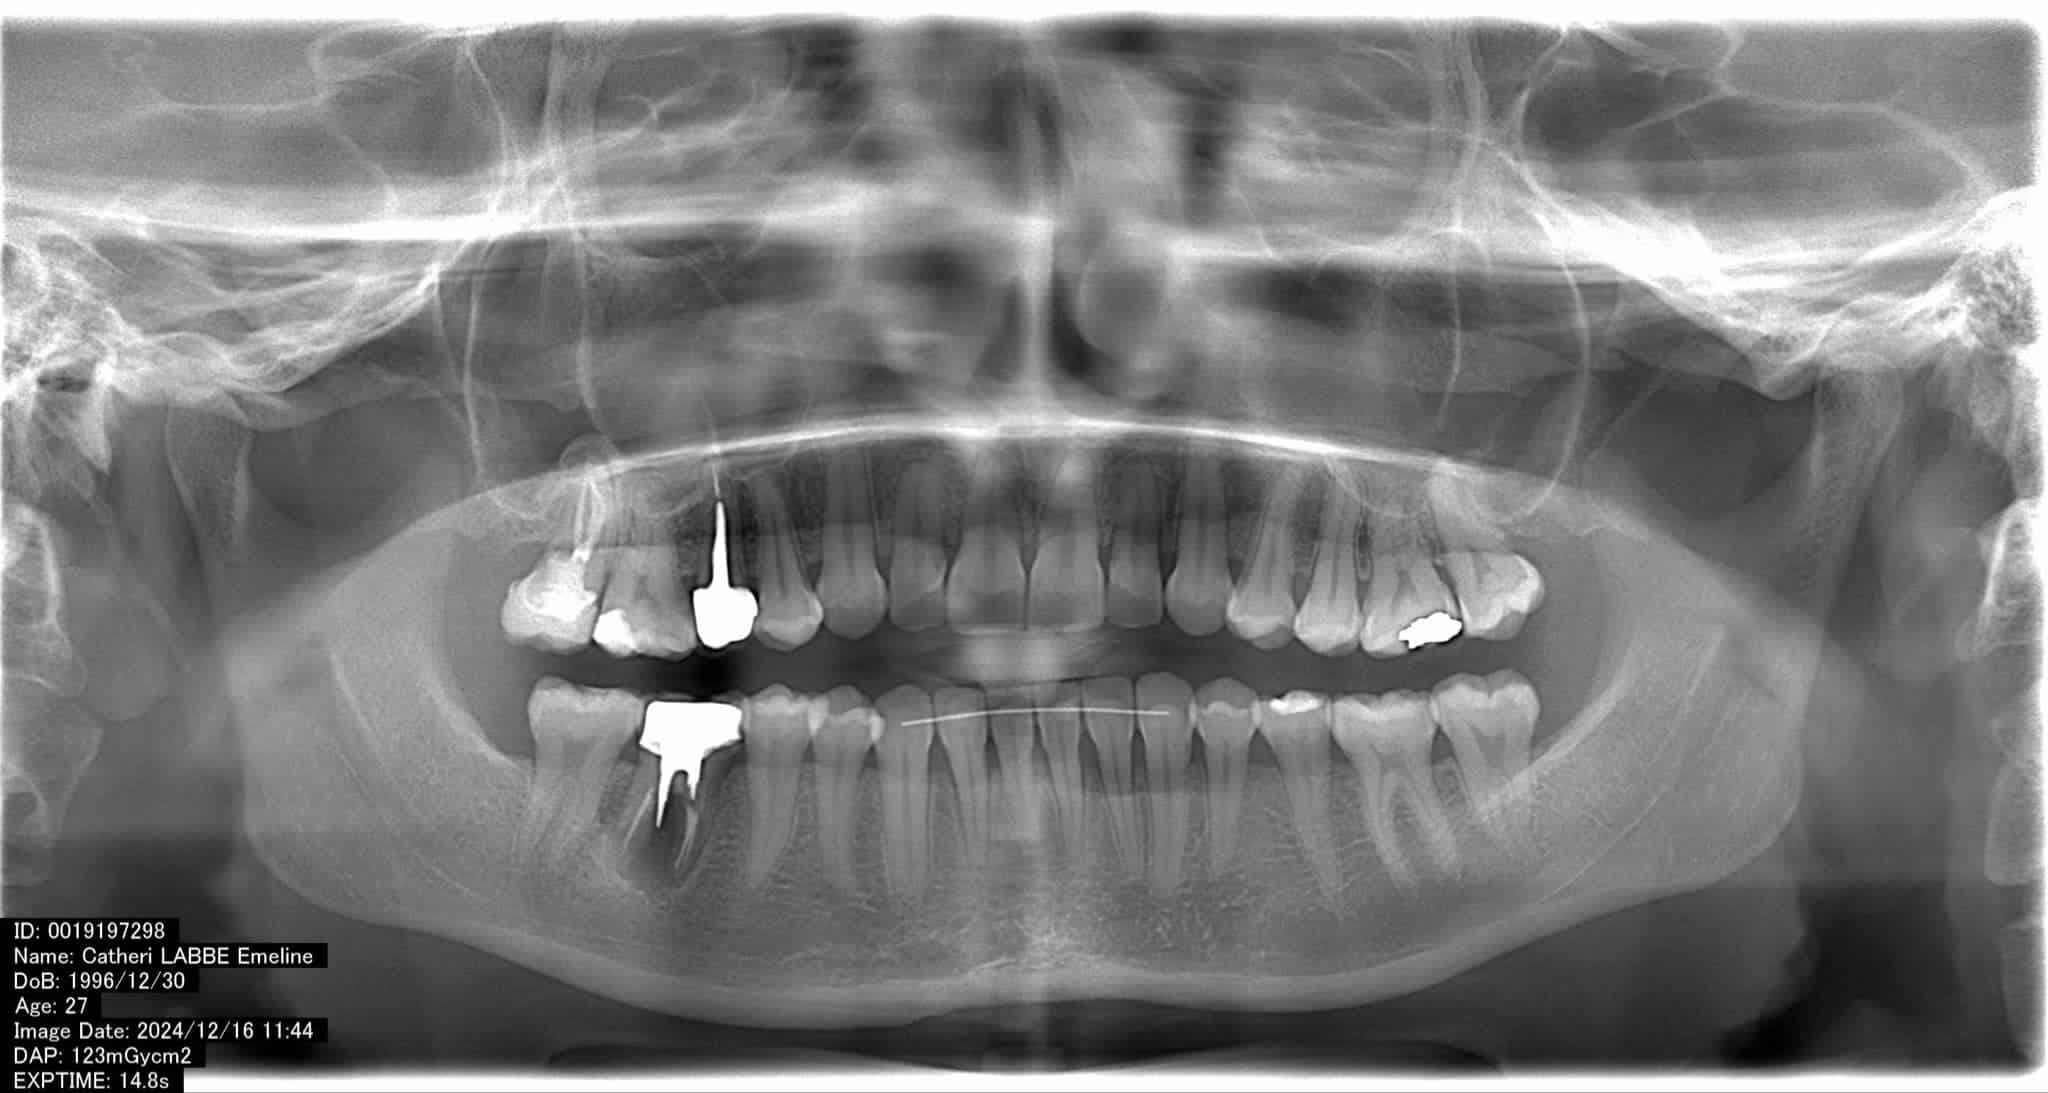

Relativement récents, les bridges collés cantilever postérieurs constituent une alternative fixe, fiable et véritablement minimalement invasive aux implants dans les secteurs postérieurs. Cette thérapeutique qui repose sur des indications bien précises est parfois débattue avec passion sur les réseaux sociaux ou dans les congrès scientifiques. Cependant des études cliniques existent, tout comme des recommandations validées dans des journaux internationaux. Leur succès repose sur des préparations et des principes biomécaniques rigoureux, pourtant simples à intégrer au quotidien. Cette intervention propose un guide clair et opérationnel incluant indications, étapes clés, protocoles d’adhésion et réglages occlusaux pour les mettre en œuvre avec confiance et reproductibilité.